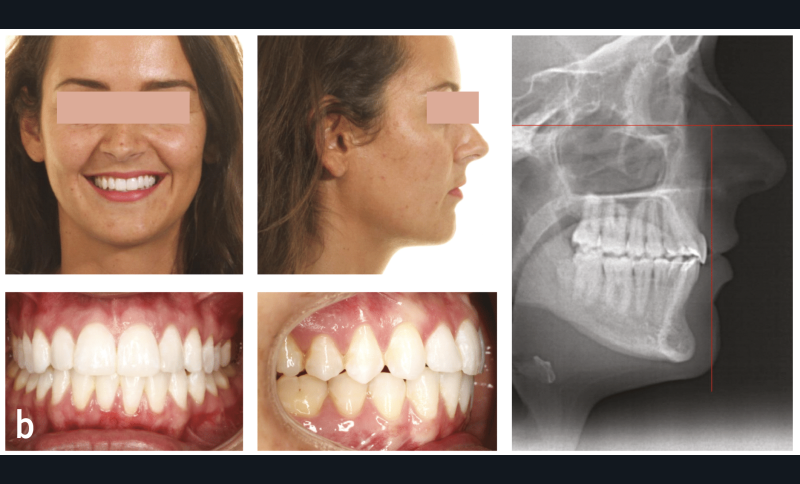

La céphalométrie aide au diagnostic. De manière simplifiée, sur une téléradiographie de profil, le plan de Francfort puis le plan antérieur de Cocconi, qui passe par le point le plus antérieur de l’os maxillaire, sont tracés ; la ligne qui passe par la face vestibulaire de l’incisive centrale maxillaire doit être tangente à ce plan (fig. 1). L’incisive centrale mandibulaire doit être au contact de son antagoniste. Si, à la suite de la simulation de cette analyse, l’incisive du bas est en dehors de l’enveloppe osseuse, cela implique le choix thérapeutique d’une chirurgie orthognatique du maxillaire et/ou de la mandibule (fig. 2).